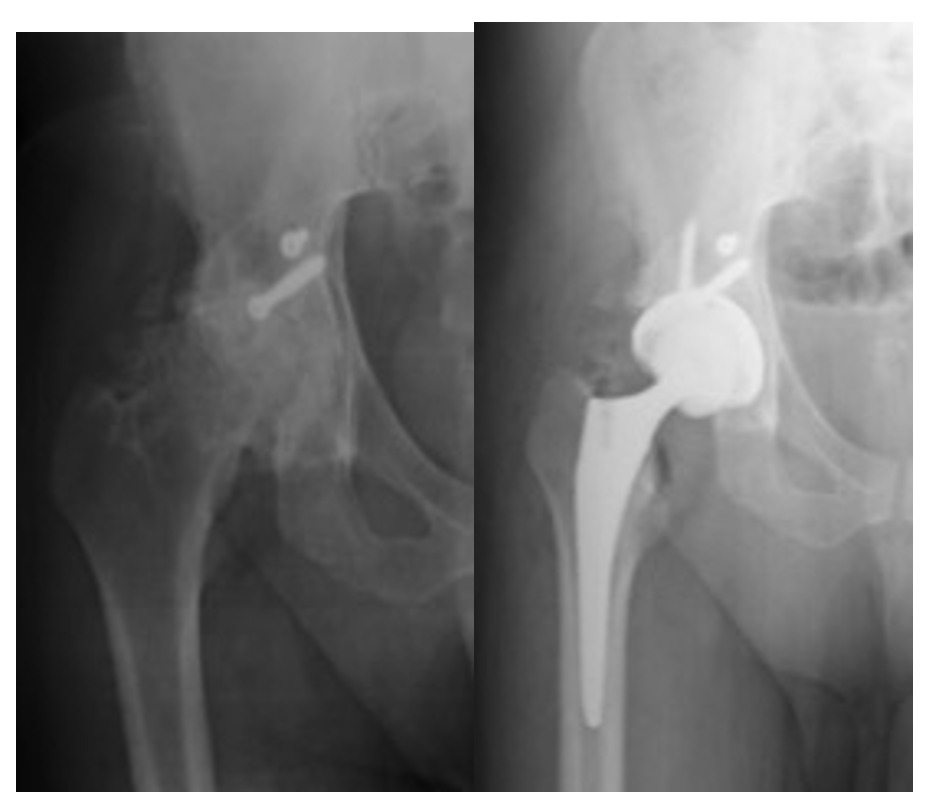

38 patients, 27 males and 11 females, ranging between 42 and 70 years old, benefited from THA. 32 for coxarthrosis, 6 for avascular necrosis of the femoral head, all secondary to an acetabular fracture (Fig.1a-b). 31 had undergone previous ORIF, 7 were treated conservatively. 4 patients underwent partial osteosynthesis material removal prior to the THA. One patient, suffering from aseptic necrosis, had undergone a decompression of the femoral head, without any results.